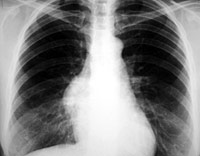

ESQUEMA 28 Comentario placa 28 La masa esta en contacto con el corazón ya que no se ve la silueta del borde derecho de éste. Los ángulos que forma la masa con el borde del mediastino son obtusos, lo que sugiere que el tumor no se origina en el pulmón sino más bien en el mediastino, paro esta diferenciación no es siempre segura. Pase a la placa lateral N° 29 |